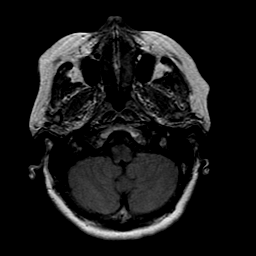

Stroke: proton density-weighted MR #1 -- Slice #3

[Home][Help][Clinical] Slice 3